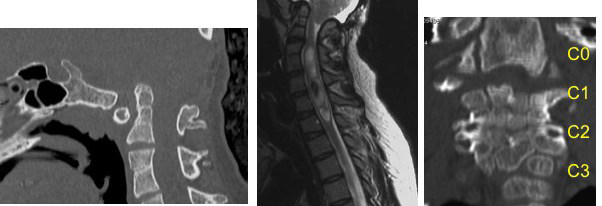

- malformation du tronc cérébral, de l’encéphale

encéphalocèle occipitale associée à des malformations multiples du tronc cérébral et de l’encéphale ; noter l’hypoplasie mandibulaire : syndrome de Pierre Robin d’origine centrale, absence de ventilation spontanée à la naissance. - malformations rachidiennes de type Klippel-Feil et hémivertèbres